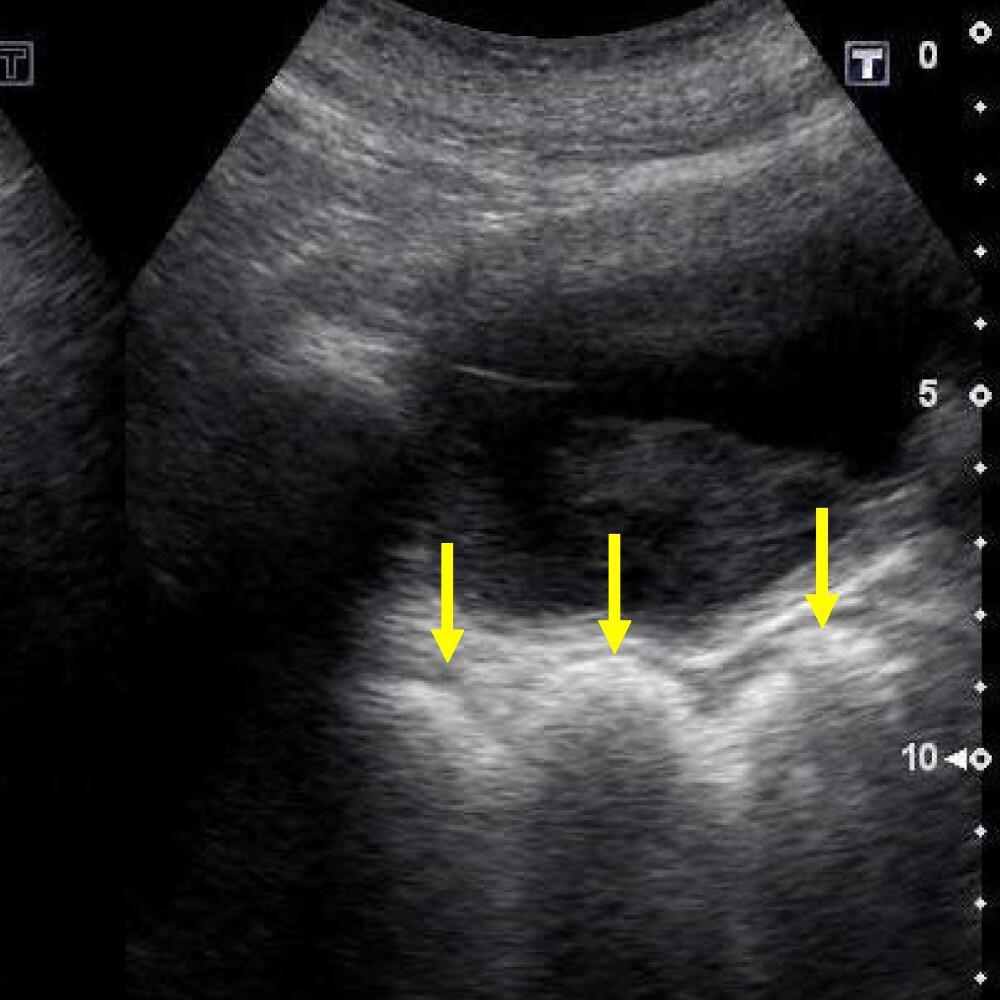

![]()

Coupe transversale montrant une rétention de selles à gauche (image hyperéchogène), un fécalome au milieu (image en demi-lune avec cône d'ombre) et un rectum vide à droite. Source : Matsumoto M et al., Diagnostics, 2022;12:300.